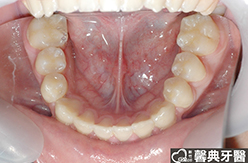

患者︰黃小弟弟,十三歲,學生。

主訴︰戽斗,想做矯正。

治療計劃︰上顎前牙排齊後彈出,下顎前牙排齊後後縮,重建正常咬合關係。